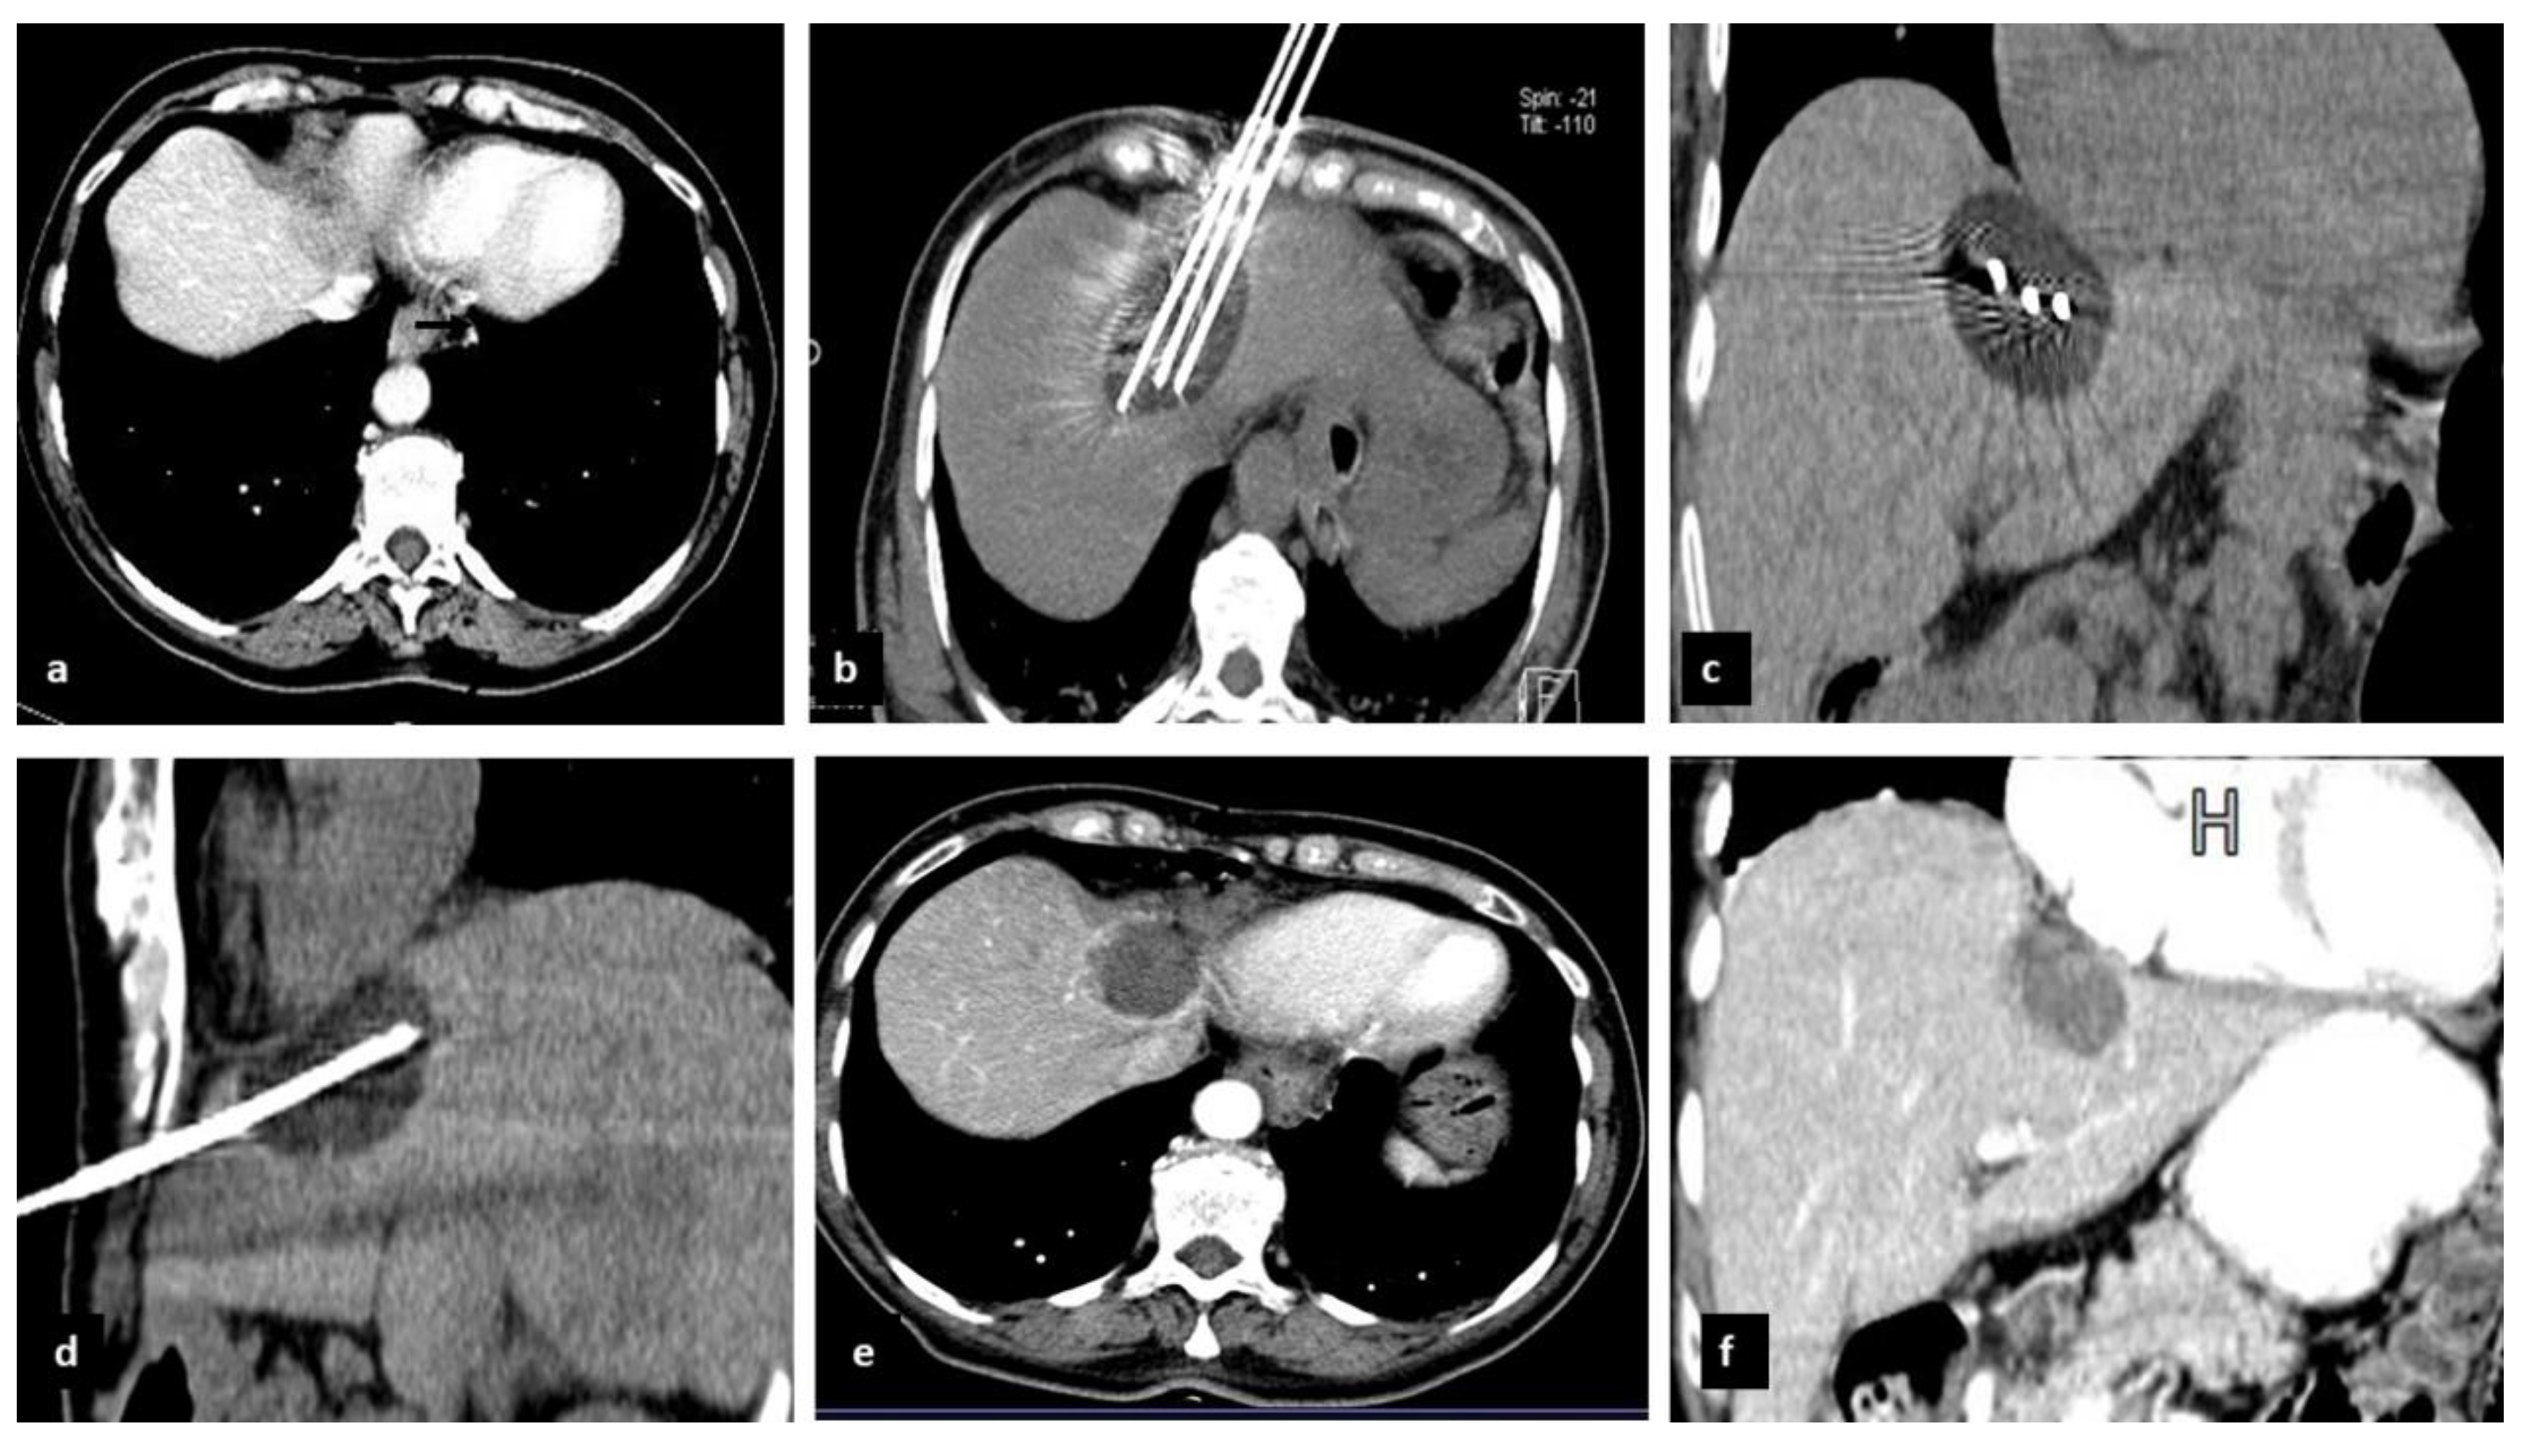

2.2. Preoperative Evaluation and CrA Procedure